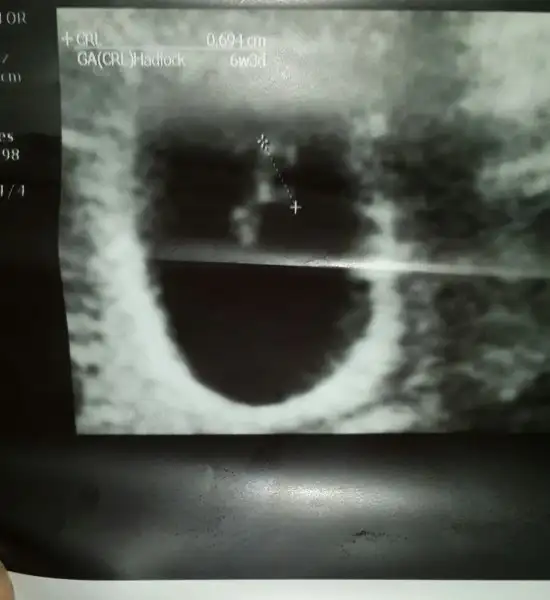

Keseye gore kiz ...Canim buda 9+5 gunluk hali bi bakarmisin karindan bakti dr tekrar bi bakar misjn canjmHavalianne__

Iste bu canimCanim benim ikiside ustten bakilan usg bugun kalp atislarini duyduk 7 +3 gunluk

Kiz gibiCanim buda 9+5 gunluk hali bi bakarmisin karindan bakti dr tekrar bi bakar misjn canjmHavalianne__